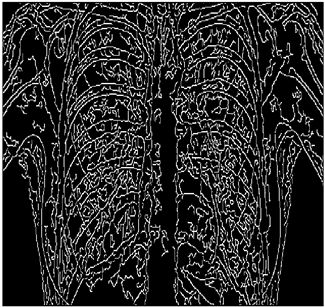

For the purpose of simulation, we consider two sets of images: (1) three images from MATLAB repository (Table 4) and (2) five X-ray images available online (Table 5).

Table 5. X-ray Images.

X-ray 1X-ray 2X-ray 3X-ray 4X-ray 5

Mathematics 10 02421 i004 Mathematics 10 02421 i005 Mathematics 10 02421 i006 Mathematics 10 02421 i007 Mathematics 10 02421 i008

Table 10. Edge-detected image of “X-ray 1” after binarization for different noises.

NoiseCannyStandardSmooth

No noise Mathematics 10 02421 i072 Mathematics 10 02421 i073 Mathematics 10 02421 i074

G(0.001) Mathematics 10 02421 i075 Mathematics 10 02421 i076 Mathematics 10 02421 i077

G(0.002) Mathematics 10 02421 i078 Mathematics 10 02421 i079 Mathematics 10 02421 i080

G(0.003) Mathematics 10 02421 i081 Mathematics 10 02421 i082 Mathematics 10 02421 i083

I(0.25%) Mathematics 10 02421 i084 Mathematics 10 02421 i085 Mathematics 10 02421 i086

I(0.5%) Mathematics 10 02421 i087 Mathematics 10 02421 i088 Mathematics 10 02421 i089

I(1%) Mathematics 10 02421 i090 Mathematics 10 02421 i091 Mathematics 10 02421 i092

As shown in Table 6, the PFOM values related to the smooth composition are higher than those of the standard composition in all cases. Table 7, Table 8, Table 9, Table 10, Table 11, Table 12, Table 13 and Table 14 also provide a visual demonstration supporting this conclusion. As is quite obvious from these tables, the density of noise in the edge-detected images of smooth composition is always less than that of the standard composition. Furthermore, the Canny edge detector is also highly prone to noises and is unable to decrease the noise density.

Table 10 shows the following:

• In all cases, the Canny edge detector detects more edge pixels than both fuzzy compositions.

• As the level of noise increases, Canny and standard composition become adversely affected by the noise, and still more edges are detected by Canny; however, most of the detected edges by Canny are misdetections due to the impact of noise. As is obvious from this table, the smooth composition provides a better image with reduced noise density.

• In all cases, the PFOM value for the smooth composition is always greater than the PFOM value for the standard composition, according to Table 6.